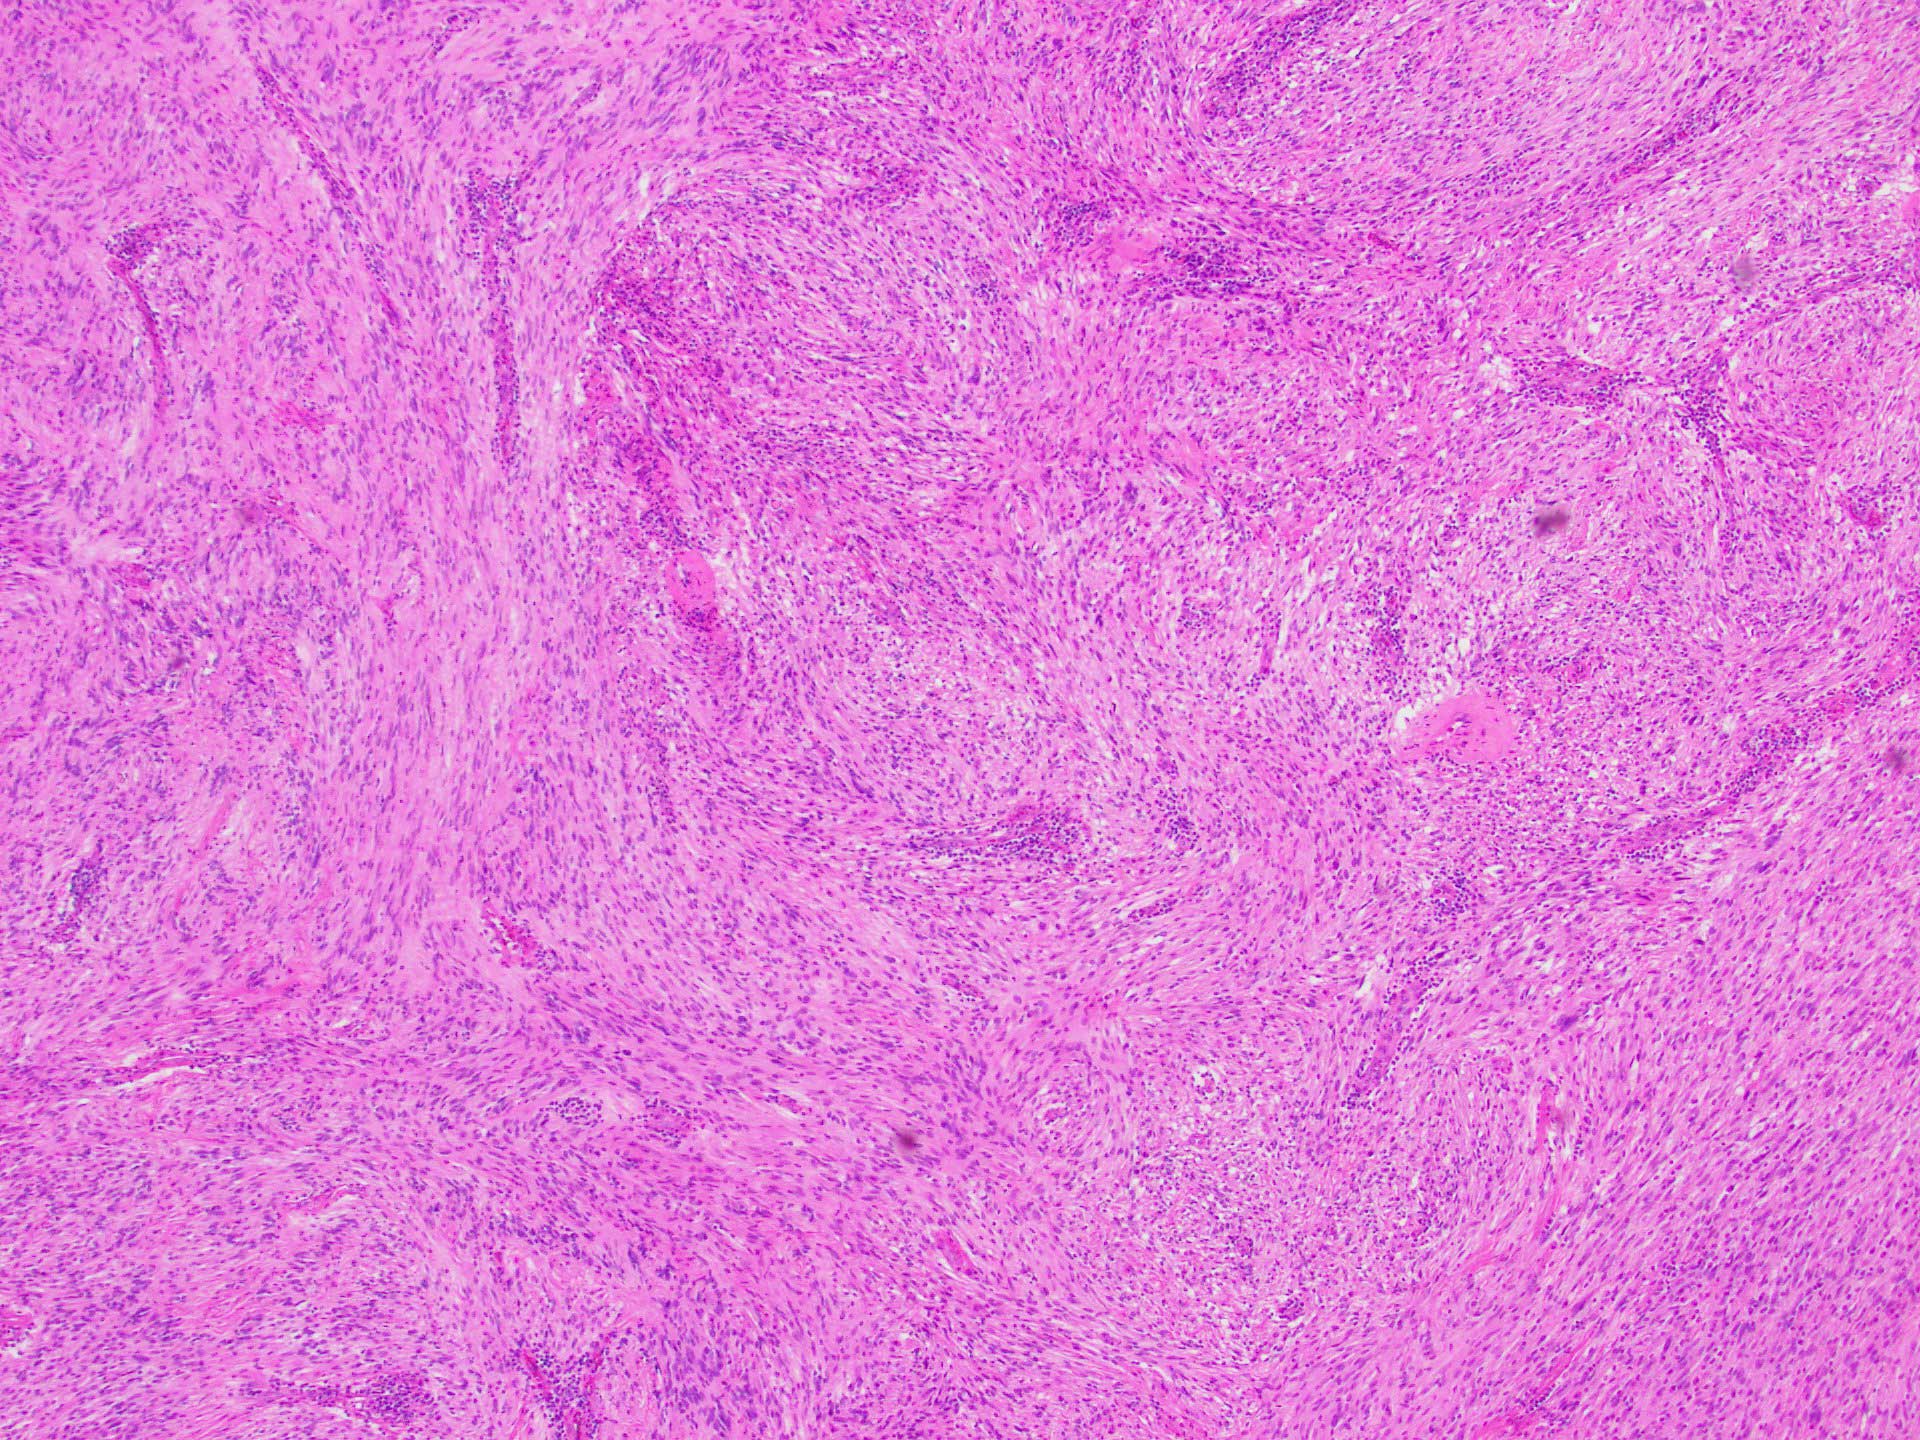

Grossly, the mass appeared as a solid dome-shaped submucosal mass measuring up to 2.7 cm (Figure 1). Histologic examination revealed a spindle cell neoplasm with foci of nuclear palisading, surrounded by lymphocytic inflammation (Figures 2-4).

Immunohistochemistry was performed and the neoplastic cells were found to be negative for C-kit (CD117) and DOG1, while strongly and diffusely positive for S-100 (Figure 5).